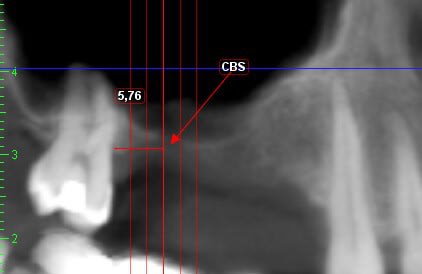

je dois pratiquer un rehaussement de plancher sinusien par volet latéral et je ne sais comment gérer le décollement de la membrane de Schneider au niveau de la communication bucco sinusale

Dès le départ, je m'inquiète au niveau du décollement du lambeau sur la CBS, on risque de déchirer à ce moment là

je joins quelques captures pour vous faire une idée

je ne vois pas de septum dans la zone de comblement

pourrais-tu préciser?